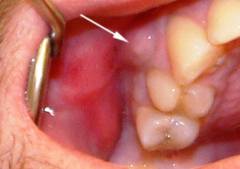

Флюс развивается на фоне поражений зуба или пародонта.

Признаки флюса:

- Постоянная, непрерывная боль, отдающая в ухо.

- Повышенная чувствительность тканей.

- Нарушение жевания и речи.

- Асимметрия лица.

- Системные признаки инфекции.

Основной симптом обострения — сильная боль, не поддающаяся обычным обезболивающим.

Периостит возникает на фоне заболеваний зуба или пародонта и сопровождается болями.

Признаки перехода воспалительного процесса на надкостницу:

- Изменение характера болей. Боль при флюсе становится постоянной и усиливается, проявляясь как ноющая, пульсирующая или дергающая, с иррадиацией в ухо, кожу лица или головы.

- Повышение чувствительности тканей. При прогрессировании воспаления изменения (расширение сосудов, отек тканей, накопление активных веществ) переходят с зуба и пародонта на надкостницу челюсти, вызывая усиление болей при механическом воздействии не только в области зуба, но и на затронутом участке кости.

- Нарушение жевательной функции и речи. Эти изменения связаны с болевым синдромом, усиливающимся при движениях или нагрузках на зубы и челюсть.

- Асимметрия лица. Прогрессирование заболевания может привести к распространению воспаления на мягкие ткани вокруг очага инфекции (десны, щеки, ткани подбородка), что проявляется отеком и болезненностью при прикосновении.

- Системные признаки инфекции. Эти симптомы, встречающиеся при флюсе, включают повышение температуры тела до 38–39ºС (защитная реакция организма), головные и мышечные боли, усиленное потоотделение, учащенное дыхание (более 20 в минуту) и учащенное сердцебиение (более 100 в минуту).